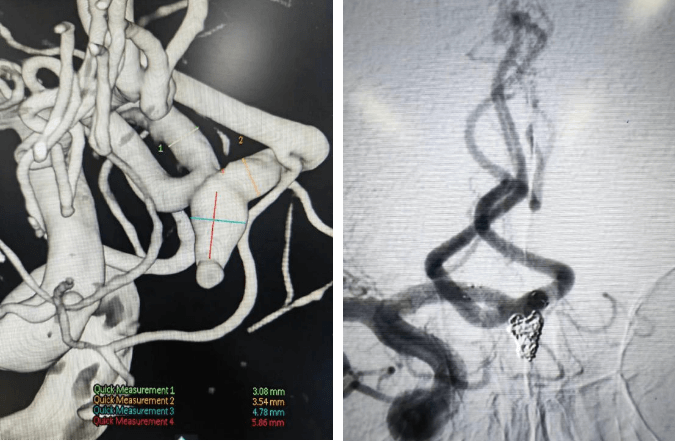

支架輔助動(dòng)脈瘤栓塞術(shù)前、術(shù)后對(duì)比

術(shù)前血管畸形及介入治療后血管畸形消失(治愈出院)